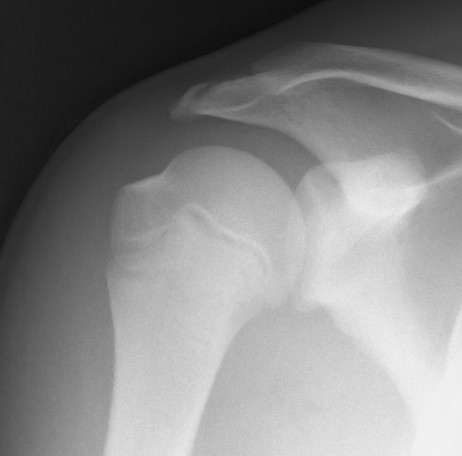

Case: 16 year old boy

Initial injury 18 months post injury